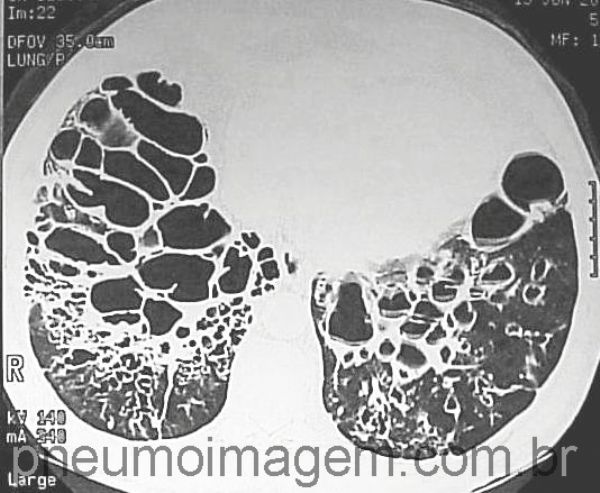

Grandes bronquiectasias císticas bilaterais, algumas com nível hidraéreo (nível líquido).

cystic bronchiectasis; air-liquid level.